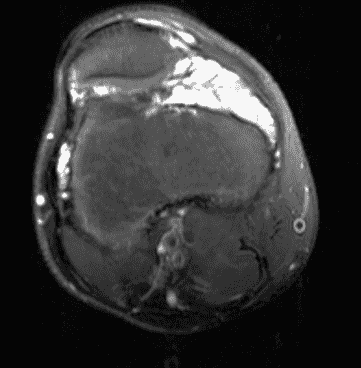

On radiographs, there may be epiphyseal overgrowth if the hemarthroses began before skeletal maturity. Bony demineralization, erosions, joint effusion, intra-osseous pseudotumors and joint space narrowing with secondary osteoarthrosis are typical findings. MRI usually demonstrates diffuse intermediate hypointense T1 and T2 signal thickened synovium with blooming artifacts due to the presence of hemosiderin with secondary osteoarthrosis changes (Figure 13).2,3,24

Figure 13: Chronic hemophilic arthropathy in the knee. (13A) Sagittal PD-weighted image shows severe arthritis with extensive full-thickness cartilage loss in the femoral trochlea (black arrow). Very low signal intensity foci in the synovium represent hemosiderin. (13B) Sagittal scout image acquired with gradient echo technique shows “blooming” artifact due to hemosiderin, most prominent in the suprapatellar recess (yellow arrow).